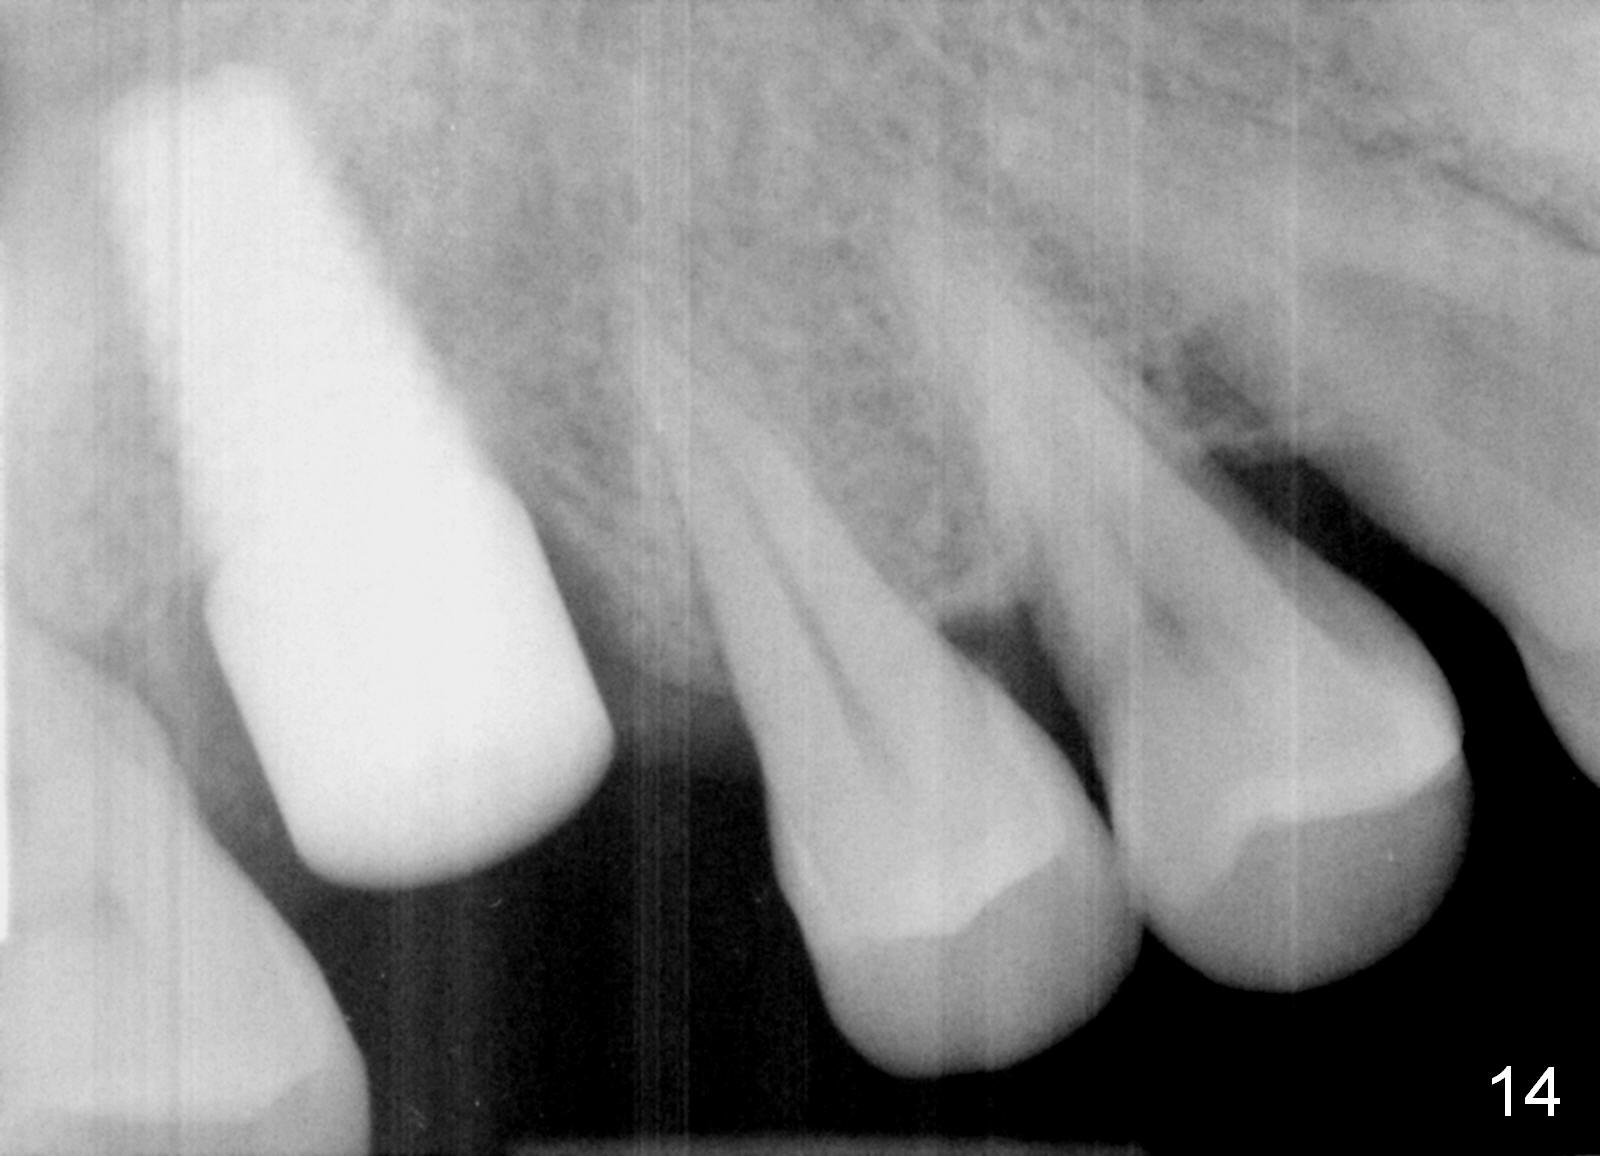

The patient returns for restoration 23 months postop; the implant appears to have been osteointegrated (Fig.14). There is no buccal or palatal gingival recession. The large implant appears to close the large defect readily and enhances bone/implant contact. The buccal plate seems to be thin 3 years post cementation, although there is no sign of periimplantitis (Fig.15). The mesial papilla is severely recessive with open contact 3 years 5 months post cementation. BW shows DO caries of the teeth #2, 4 and 30. The crown is removed for better oral hygiene by fabricating a provisional and conservative composite for #4. Water Pik is recommended.